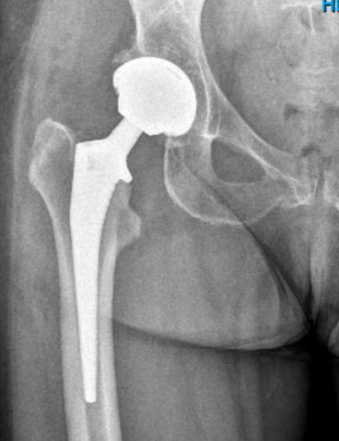

Op de operatiedag, of de ochtend hierna, wordt een Röntgenfoto van de nieuwe heup gemaakt.

Dit Röntgenonderzoek hoeft in de hierop volgende controles op het spreekuur niet meer herhaald te worden, tenzij hier een speciale reden voor is.